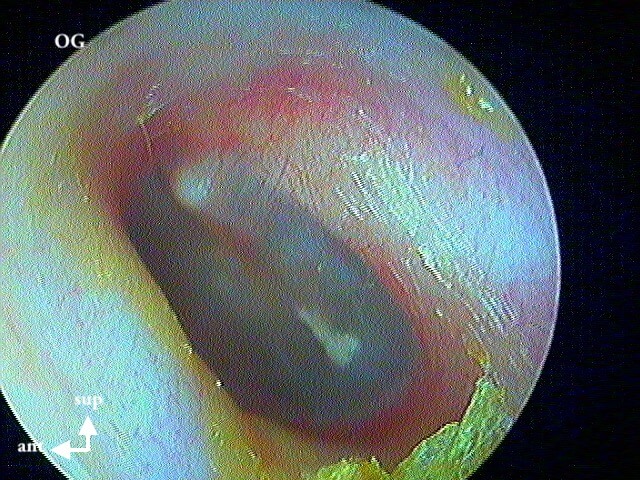

5 OTITE SÉROMUQUEUSE (OSM)

Reliefs normaux sans bombement, mais congetive avec ou sans bulle(s).

8 POCHE DE RÉTRACTION (ou ATÉLÉCTASIE)

C'est volontiers dans mon expérience la pathologie la plus importante et la plus difficile du diagnostic otoscopique pur. On bascule entre la surveillance clinique annuelle (abstention thérapeutique) et l'interventionnisme chirurgical pour éviter le cholestéatome (qui parfois est iatrogène pour l'audition résiduelle).

J'utilise plus le terme de poche de rétraction plutôt qu'otite atéléctasique.

Donc il faut caractériser ces poches de rétraction (+/- associée à myringosclérose, perforation tympanique, OSM) par:

1/autonettoyante: non cholestéatome

2/ mobilisable au Valsalva: pas d'aérateur (juste surveillance annuelle)

3/ contrôlable à l ’optique: pas de tympanoplastie (DANGER si on ne voit pas le bout de la poche qui s'invagine: risque de cholestéatome)

4/ localisation: pars flaccida (rétraction atticale ou épitympanique) ou pars tensa (rétraction atriale ou mésotympanique)